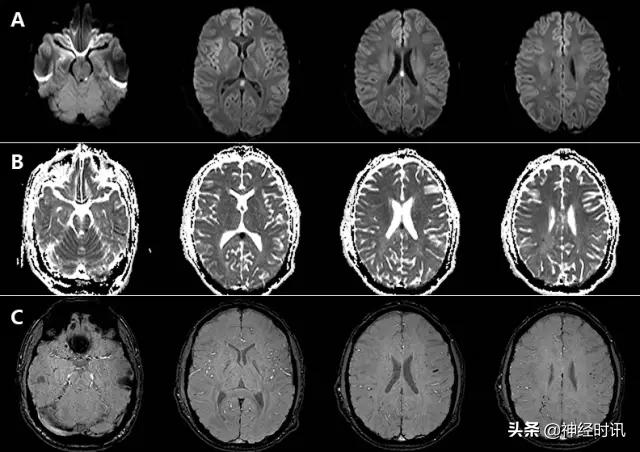

东部马脑炎

这是一种蚊子传播的虫媒病毒,临床表现可从感冒样症状、意识模糊和嗜睡,到神经功能缺损、癫痫发作和昏迷。约5%感染导致脑炎,1/3患者死亡,存活患者遗留明显残疾。典型病灶出现在双侧基底节、丘脑和脑干T2-FLAIR高信号(图11)。皮层和脑室旁白质受累相对少见。

图11 一例43岁男性,发热、头痛、精神状态改变2天,发病2天前曾野营。入院MRI显示双侧基底节、丘脑和岛叶T2-FLAIR(A)高信号和轻度弥散减低(B:DWI,C:ADC),左侧重于右侧。数天后MRI显示更为广泛的基底节和岛叶皮层受累(D:FLAIR)。